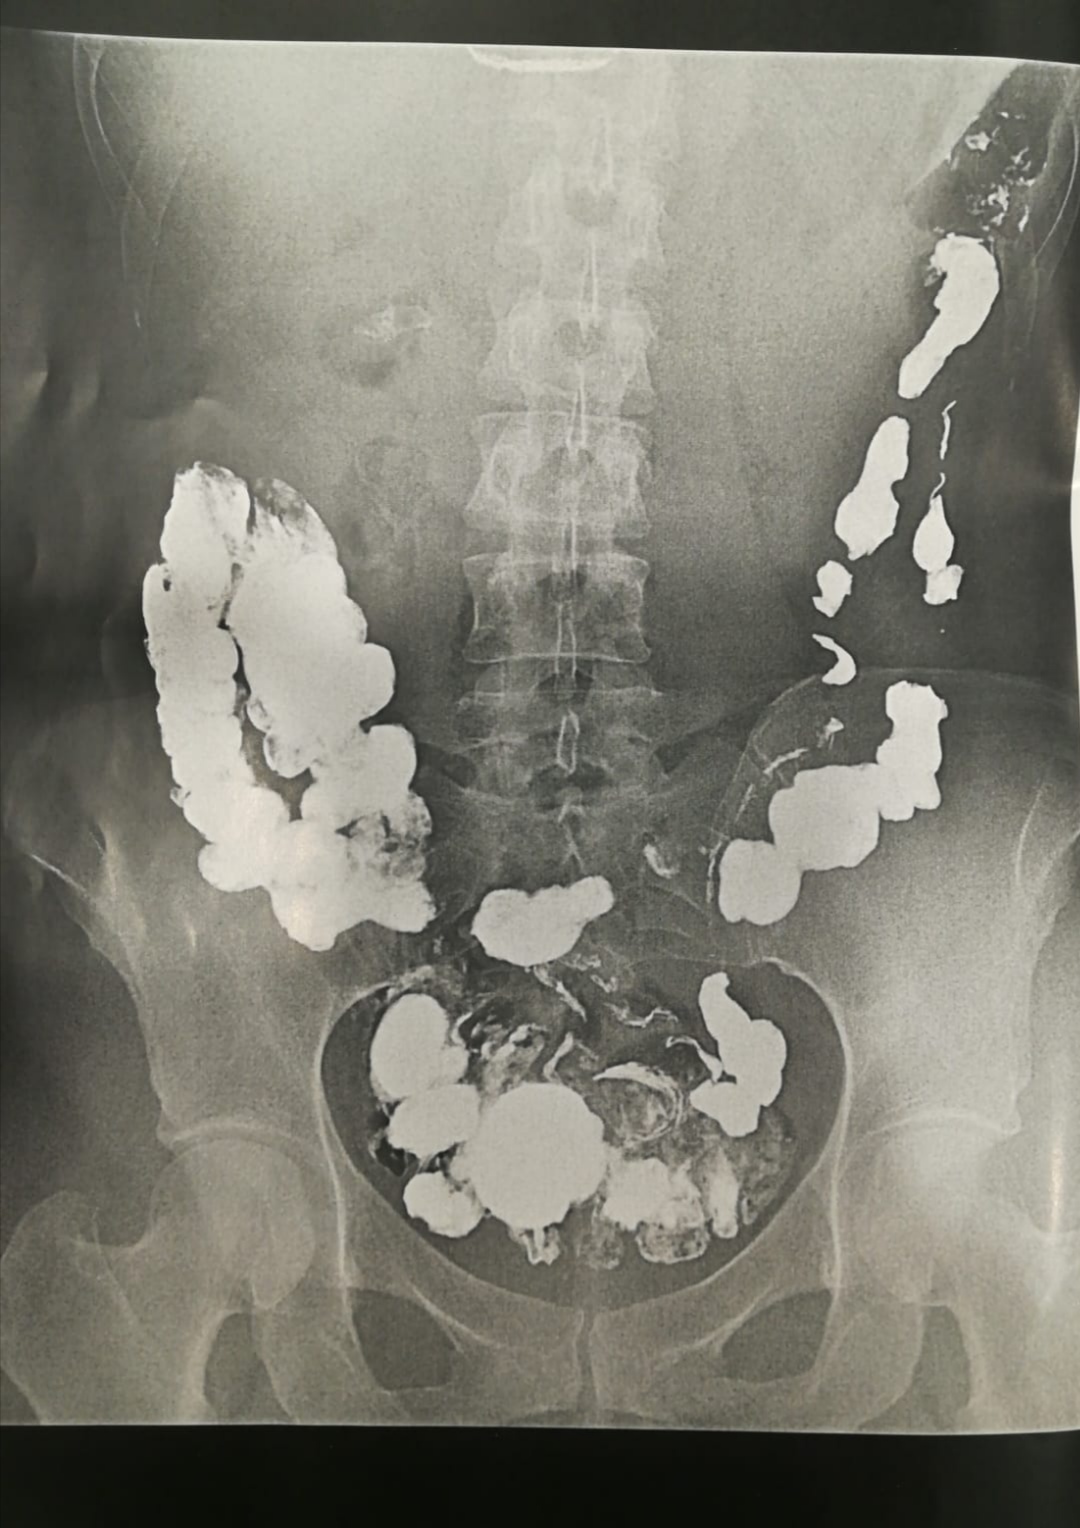

Son muchas las causas que pueden originar estreñimiento crónico de cualquier tipo, es decir, que disminuya el número de veces que se va al baño por semana, que se aumente la consistencia de las heces y haya que hacer más esfuerzo al defecar, que haya que ayudarse con los dedos para que se vacíe la ampolla rectal, etc...

Cuando las medidas y los tratamientos convencionales no son efectivos y tu estreñimiento no mejora después de 3-6 meses, deberías buscar un especialista en la materia y que te valorara. A veces se padece una enfermedad cuya primera manifestación es el estreñimiento y para llegar al diagnóstico habría que realizar algunas pruebas complementarias para su diagnóstico; la más temida es el cáncer de colon, cáncer de recto o cáncer anal, pero hay otros muchas como por ejemplo: diabetes mellitus, hipotiroidismo, mala absorción de electrolitos y vitaminas, síndrome de intestino irritable, traslocación bacteriana (SIBO), demencia, depresión, y un largo etcétera.